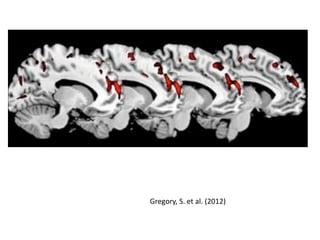

Gregory, S. et al. (2012)

Gregory, S. etal. (2012)

• #16 Areas of reduced gray matter volume in the temporal pole (above) and medial prefrontal cortex (below) and areas of the brains of the psychopathic group of antisocial men (ASPD+P) compared to the non-psychopathic group of antisocial men (ASPD-P).